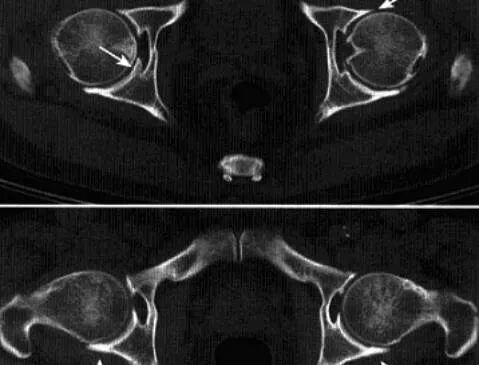

快速破坏性髋关节病

是一种不知确切病因而侵犯股骨头及髋臼导致髋关节在短时间内快速破坏的髋关节疾病。

病理:股骨头变小,负重区扁平,关节面软骨消失,软骨下骨破坏、碎片状骨坏死,骨小梁硬化、增粗。

临床表现:多发生于60岁以上老年女性,多一侧发病,无明显原因髋关节疼痛,之后逐渐加重,后期出现功能受限和跛行。

影像诊断:首选X线平片,髋关节正位及蛙式位。

1、平片:髋关节间隙进行性消失是本病特征;早期股骨头无明显变化,数月间股骨头上方进展性破坏吸收,股骨头变扁,无囊变,骨赘增生不显著,周围软组织无明显异常。

2、CT:股骨头负重区骨质溶骨样改变,骨质碎裂的,关节面软骨大片状剥脱皲裂,头*骨质呈小圆形颗粒状改变,软骨下骨的连续性破坏,头外形不规则缺损,碎骨片线状分离。

3、MRI:股骨头及髋臼骨质吸收伴软骨丢失,股骨头向上外方移位,关节内积液,骨髓未见明显异常。